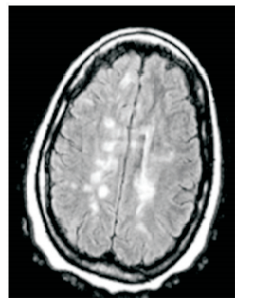

Paciente do sexo feminino, 30 anos, previamente hígida. Apresentou quadro súbito de perda da visão do olho direito com recuperação total em 15 dias. À época não foi feita nenhuma avaliação neurológica. Após seis meses, a paciente apresentou quadro de tonteira e a seguinte imagem é encontrada em sua ressonância magnética de crânio: enunciado 598723-1

Com base na história clínica e na imagem, é necessário investigar qual doença neurológica?